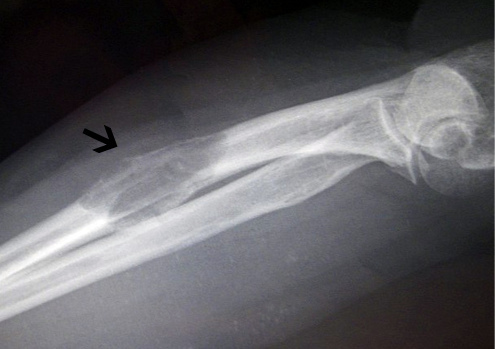

После визуального и мануального обследования пациенту, как правило, назначают пройти рентгенографию, компьютерную и магнитно-резонансную томографию. Эти методы изучения костной ткани позволяют определить границы, структуру и локализацию злокачественного процесса.

В большинстве случаев, костные опухоли ноги в начальном периоде протекают бессимптомно. Травмы стопы, которые имеют злокачественное поражение кости, вызывают острые приступы боли. На более поздних стадиях заболевания опухоль вызывает ослабление костной ткани, что приводит к частым переломам стопы. Боль является основной жалобой пациентов. Она может быть тупого, ноющего характера и донимать человека предпочтительно в ночное время.